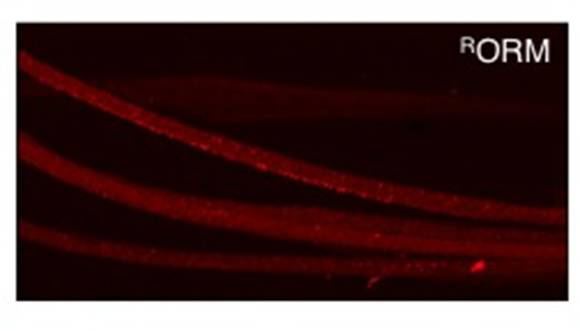

The bright red spots in this confocal microscopy image are clusters of ORMOSIL particles in axons of fruit fly neurons. Photo courtesy of Shermali Gunawardena and PLoS One.

BUFFALO, N.Y. -- In the images of fruit flies, clusters of neurons are all lit up, forming a brightly glowing network of highways within the brain.

It's exactly what University at Buffalo researcher Shermali Gunawardena was hoping to see: It meant that ORMOSIL, a novel class of nanoparticles, had successfully penetrated the insects' brains. And even after long-term exposure, the cells and the flies themselves remained unharmed.

The particles, which are tagged with fluorescent proteins, hold promise as a potential vehicle for drug delivery.